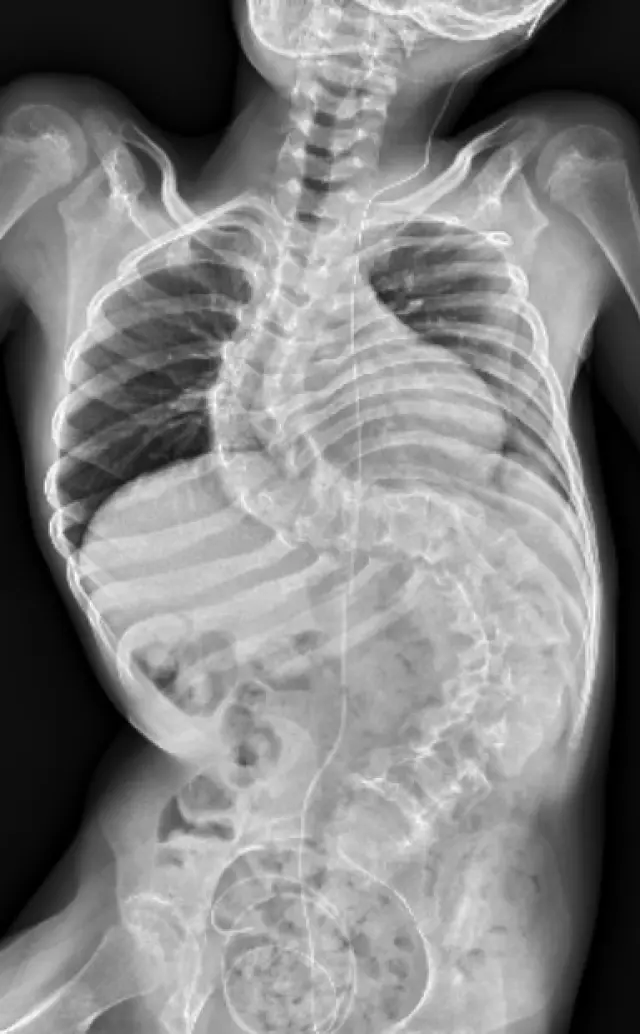

Těžká skolióza

Velký zdravotní problém, který s DMO souvisí, je těžká a život ohrožující skolióza. Ronji křivka je 115 stupňů, což znamená, že je úplně zlomená v pase a utlačuje plíce a vnitřní orgány. Operace je natolik náročná a v jejím případě také tolik riskantní, že se k ní lékaři neodvážili a nebo ji vůbec nedoporučují. Od 5. měsíce cvičila Ronja Vojtovu metodu, podstoupila několikrát lázeňskou léčbu a řadu neurorehabilitací. Nyní prochází růstovým spurtem a její pohyb potřebuje výraznou podporu.